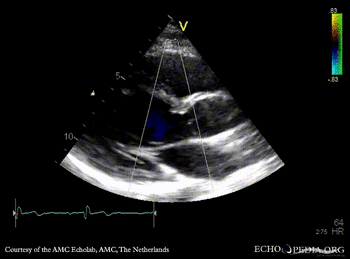

E00727.gif E00728.gif

PSAX: subvalvular membrane PSAX with Color Doppler: high velocity flow in LVOT